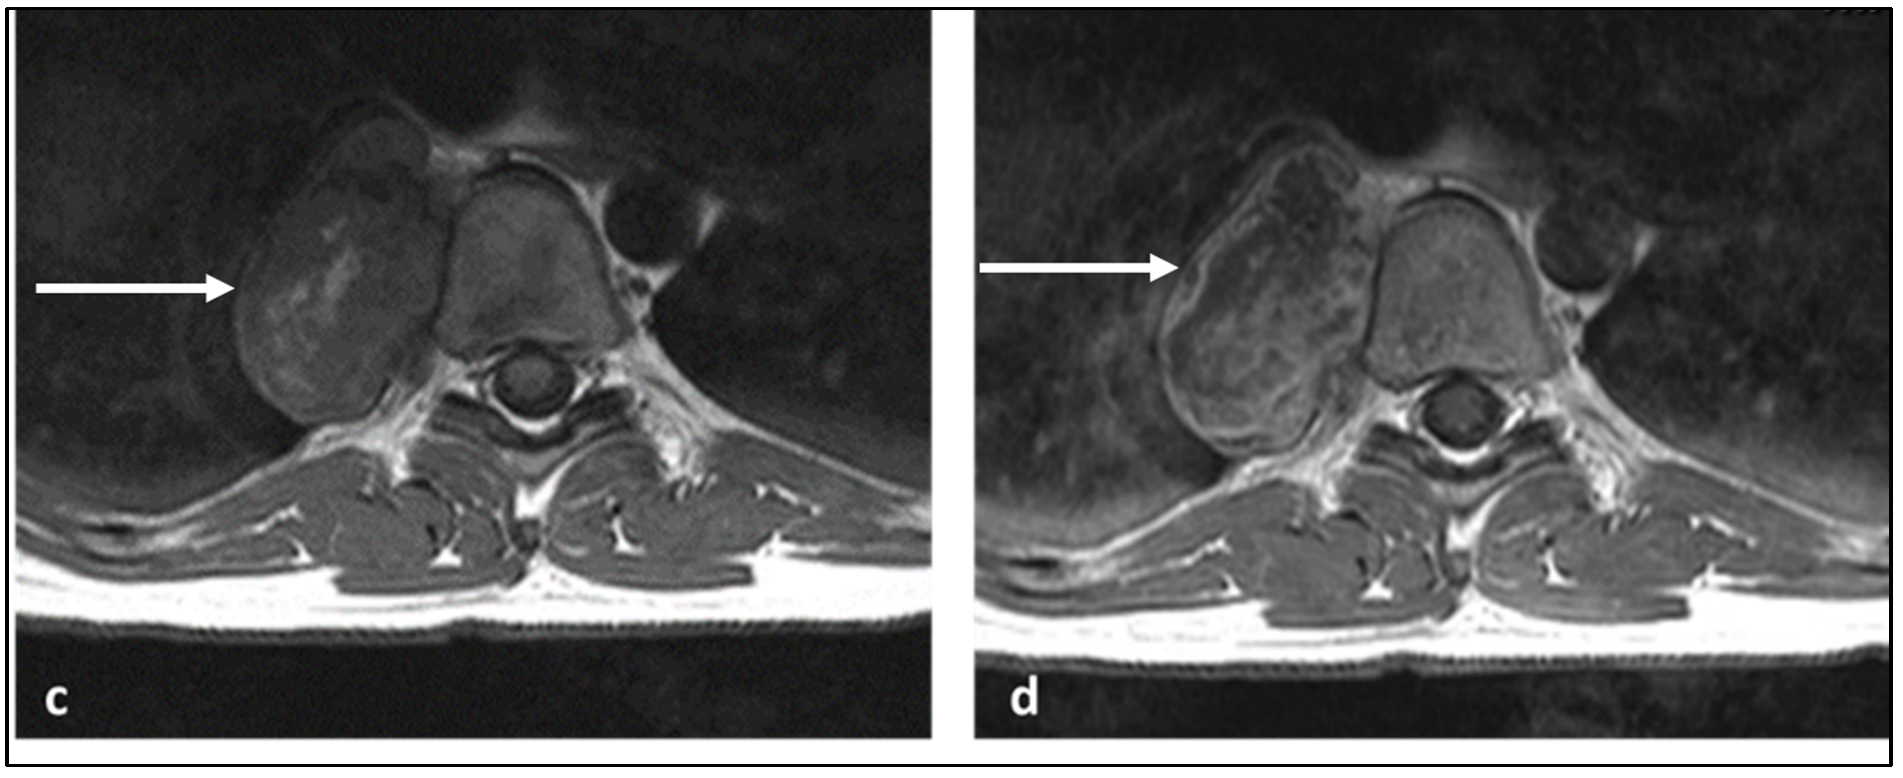

| Ewing sarcoma | Lytic lesion. Vertebral collapse. | Low to intermediate signal T1 and intermediate to high signal T2 lesion. Enhancing extra-osseous soft tissue component. |